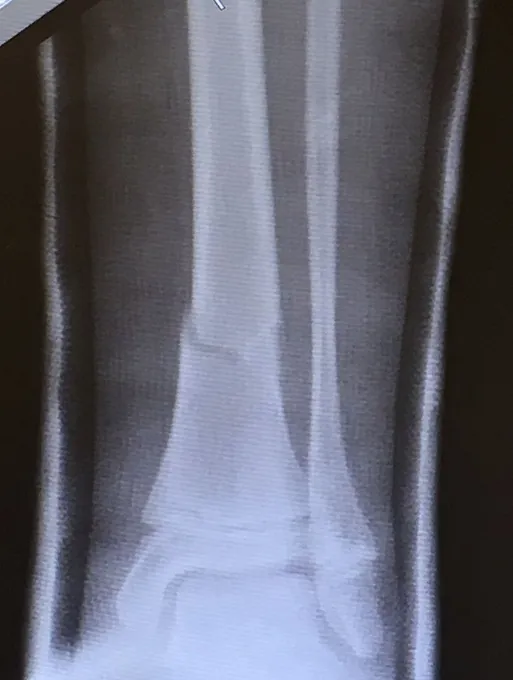

Below, Tibia and Fibula Fracture in a 16-year-old injured skiing. The patient presented to the office 8 days after injury with a displaced fracture. The first 2 films show the displacement in the fracture of the tibia. After an above knee cast is applied, the cast is wedged under fluoroscopy and new xrays show the near perfect reduction of the fracture. The white arrows show the area where the cast is wedged

Xray of Tibia Fracture